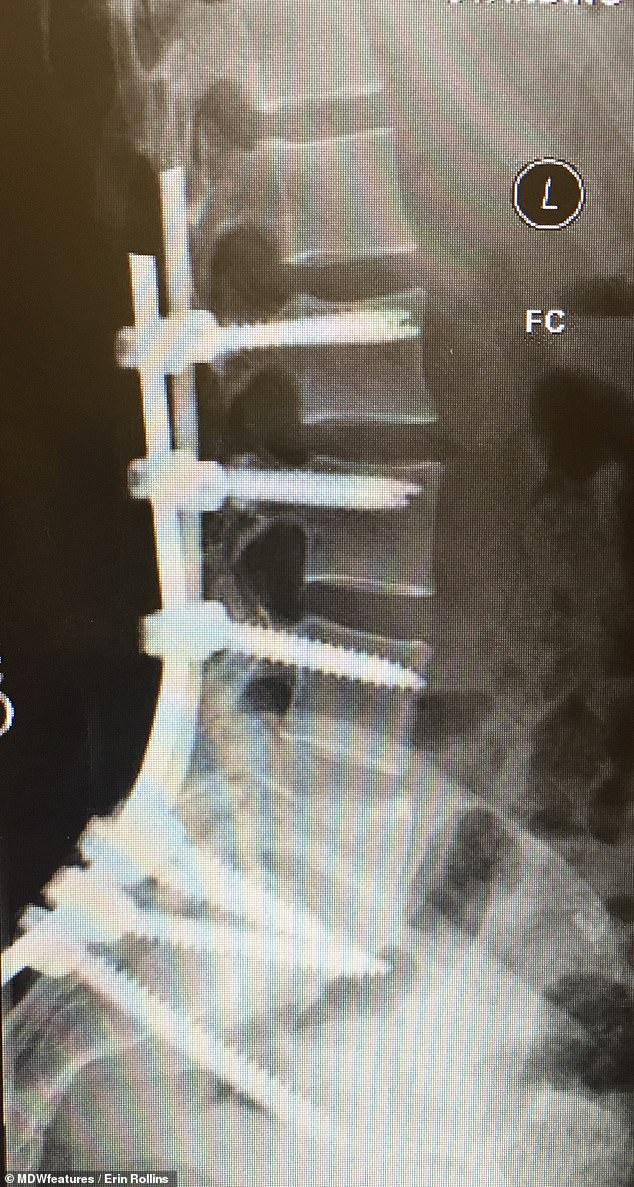

罗林斯女士已经做了8次手术,包括2016年的背部手术,她将金属棒植入脊柱,以防止脊柱塌陷。

车祸使罗林斯太太的生活陷入停顿,她花了数年时间恢复体力。她做过各种各样的手术,包括两次插入脊柱棒以防止脊柱塌陷。2017年,外科医生认为她的脊柱是安全的。